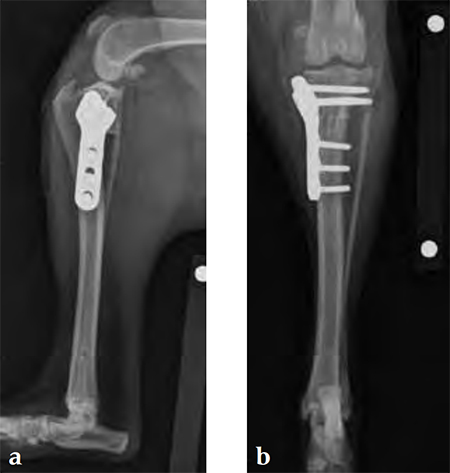

Case 1: English bulldog

(Case provided by Brian Beale, Houston, USA)

A 4-year-old, female, spayed, 33 kg English bulldog had a CrCL tear and a medial patellar luxation. The small stature 3.5 mm TPLO plate was perfect for this dog due to the small profile of the bone and the need to use a heavier plate (3.5 vs a 2.7 mm). In the past, veterinary surgeons have been forced to either squeeze the standard TPLO 3.5 mm plate on the bone or use an undersized TPLO 2.7 mm plate. In this patient, the shorter and smaller profile head of the small stature TPLO 3.5 mm was perfect.